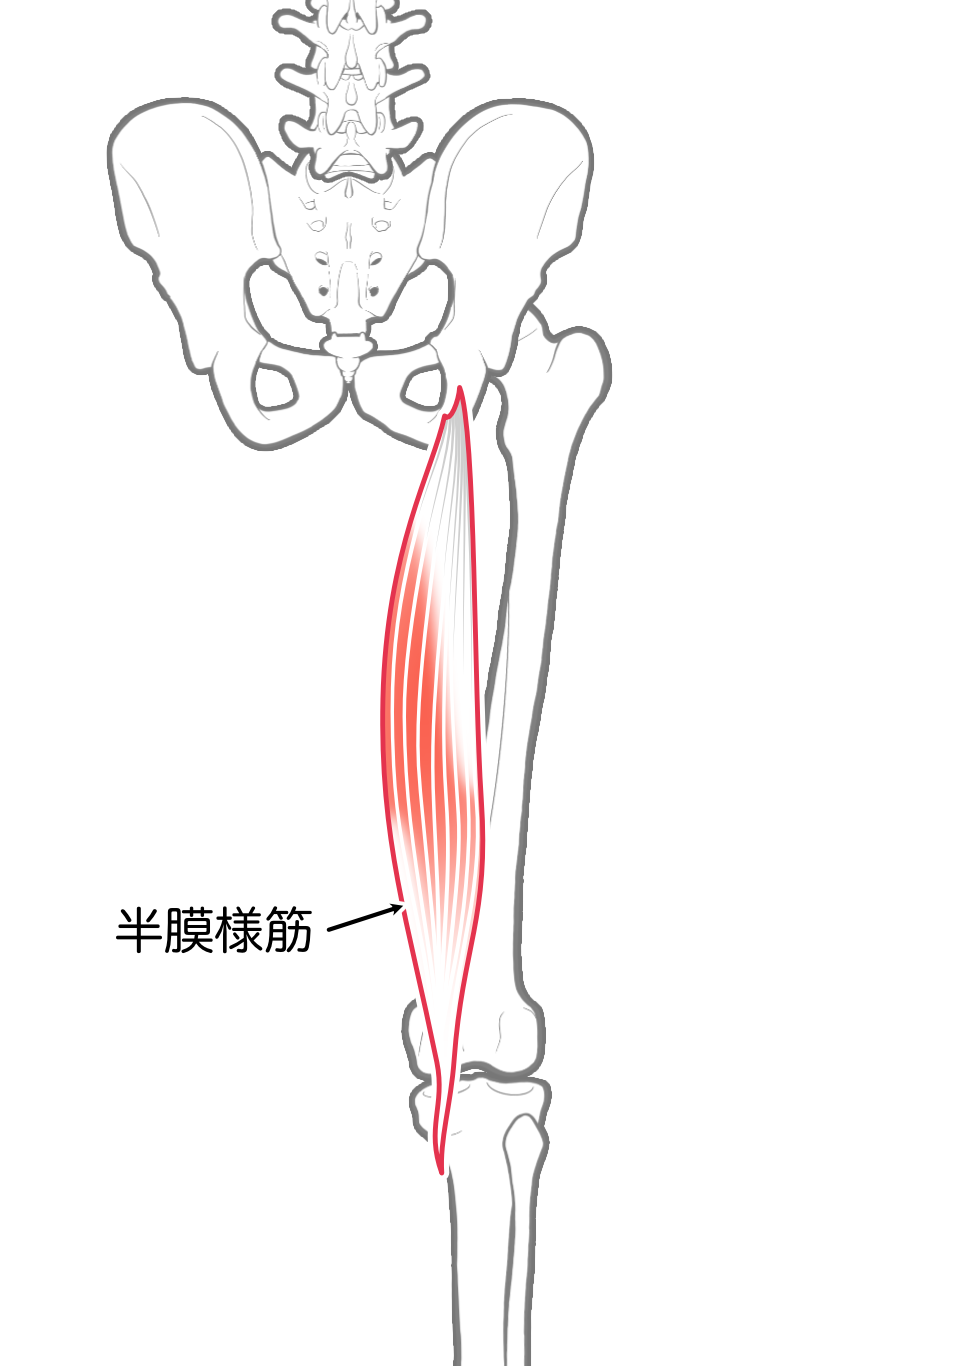

半膜様筋

| 起始 | 坐骨結節 |

| 停止 | 脛骨内側顆, 斜膝窩靱帯 |

| 神経 | 坐骨神経L4-S1 |

| 作用 | 膝関節屈曲,内旋 |